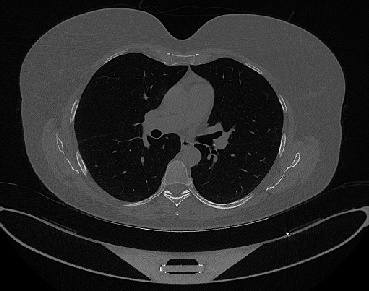

It should be mentioned that for explainability purposes [7, 8, 9], an anchor set was generated for the COV19-CT-DB database [5]. This included 11 anchors, each representing a respective 3-D CT scan obtained through an appropriate clustering procedure. Figure 2 shows a series of slices from a COVID-19 case, whereas Figure 3 shows a series of slices from a non COVID-19 case.